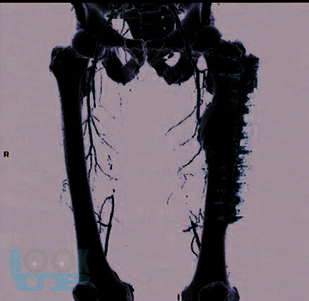

В учебном пособии раскрыты клинические особенности пациентов с окклюзирующими заболеваниями артерий нижних конечностей; представлены клинические и лабораторные методы исследования. Особое внимание уделено медицинской реабилитации пациентов после бедренно-подколенного шунтирования.